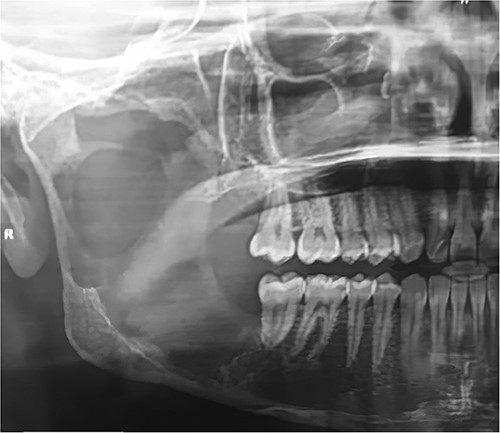

A 22-year-old male patient presented to the Oral and Maxillofacial Surgery Department at Tishreen University Hospital with chief complaints, recurrent fistula at the right retromolar area and clear yellow liquid discharge intraorally from the fistula 1 year ago. The patient was recommended an Orthopantomogram (OPG) which showed radiolucent lesion, including most of the right ramus area (Fig. 1). Computed tomography (CT) scan showed a cavity in the right mandibular ramus with an expansion and absence of most buccal and lingual bone plates (Fig. 2). An incisional biopsy was performed and a specimen was sent for histopathology examination. Based on clinical, radiographical and histological features, the lesion was diagnosed as an OKC.

OPG showed radiolucent lesion including most of the right ramus area.